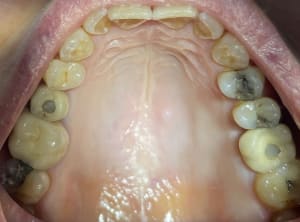

mise en charge immédiate 10.jpg